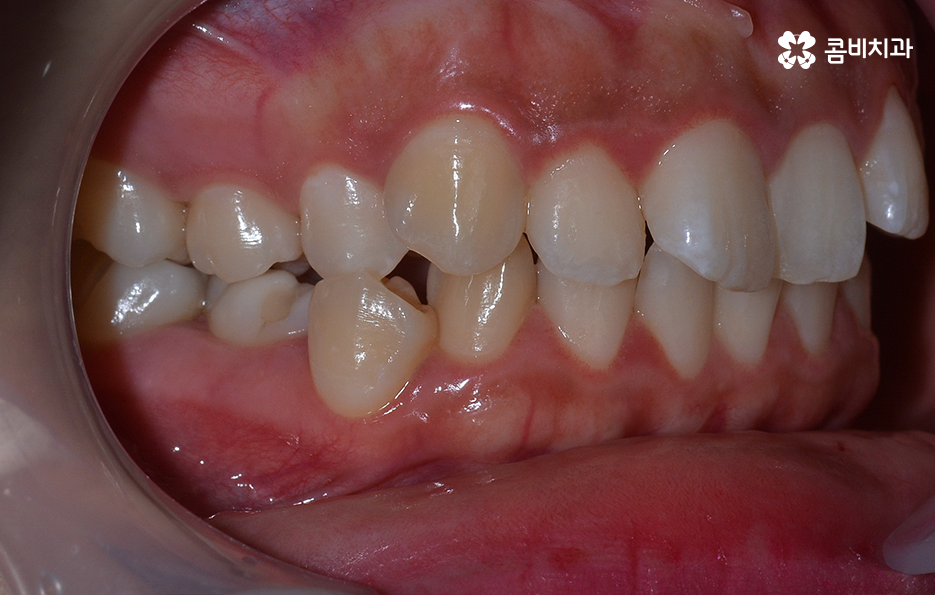

덧니는 윗니와 아랫니에 모두 있거나 앞니에 살짝 있는 수준의 덧니도 있으며 덧니가 심한 경우에는 개방교합으로 인해 입이 잘 다물어지지 않는 경우도 있기 때문에 덧니가 심한 정도에 따라서 치아교정의 계획은 세부적으로 달라질 수 있어요

덧니가 심하지 않은 경우에는 비발치로도 충분히 교정을 하는 경우도 있겠지만 덧니가 심한 경우에는 덧니 발치 교정을 통해서 치료가 진행되는 경우가 많이 있는데요. 그 이유는 치아교정의 원리를 생각하더라도 치아를 재배치하기 위해서는 기존의 치아가 움직일 공간이 필요한데 덧니는 치열이 이미 완성되고 있는 상태에서 치아가 나올 공간이 부족하여 덧니가 되는 경우가 많다는 점에서도 치아의 이동 공간을 확보하기 위한 발치가 필요할 수 있는 거예요

물론 덧니 발치 교정을 하는 사례가 보편적으로 많은 편이긴 하지만 무조건 발치 교정이 좋은 것은 아니고 꼭 해야 하는 것은 아니라고 할 수 있는데요. 앞서 설명드린 것처럼 치아 공간 확보가 충분히 되는 경우도 있고 얼굴형과 입술 라인을 고려할 때 발치를 하는 것이 얼굴과의 조화 부분에서 더 이로울 것으로 예상되는 경우와 발치 후 합죽이와 같이 보이는 안좋은 결과가 예상된다면 무리한 발치는 안하는 것이 좋다고 볼 거예요

치아교정 계획을 세울 때 이처럼 치아의 이동공간 뿐 아니라 교합과의 상관관계, 골격, 얼굴형을 종합적으로 고려하여 치료 계획을 세우기 때문에 발치 여부 하나만 보더라도 발치 자체가 무조건 좋고 나쁘다는 개념은 옳지 않으며 자신의 치아와 얼굴형 등을 종합적으로 판단할 때 정밀 검진 결과를 토대로 세부적인 계획이 하나씩 세워지고 있어요